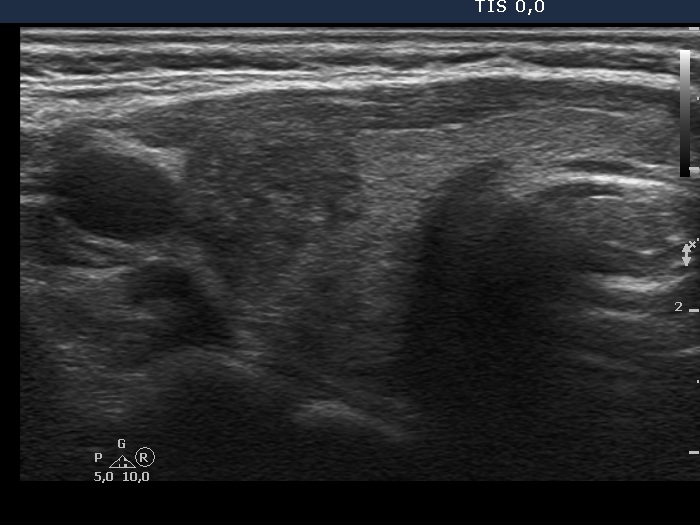

Case 374 (ultrasonographic picture 1b)

Right lobe, transverse scan. This image illustrates why video is better than still image. You can extract an image from the video at almost any time that not characteristic of the particular thyroid or, as in this case, misleading. Watching the video, it is clear that the hypoechogenic parts have fundamentally blurred borders. But this picture does not show just that. Here, the nodule appears to have a sharp, lobulated margin.